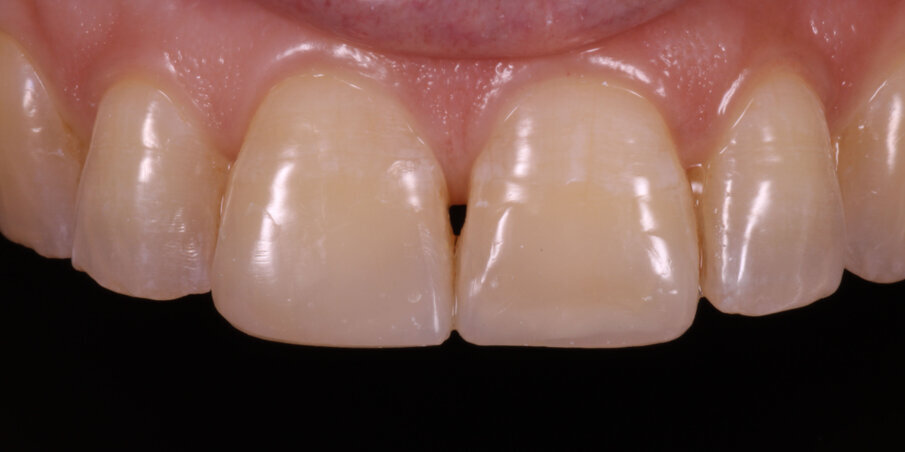

Finishing was carried out with finishing discs (Shofu Snap-on Discs) and Soflex Spirals (3M ESPE). Polishing was done with Prisma Gloss polishing paste (Dentsply) and a rubber cup (Fig 15). Thus the reverse smile was corrected by a simple restoration of fractured incisal edges. The patient reported back to us with a renewed sense of confidence after her smile-rejuvenation (Fig 16-17).

Fig 16. Two-week post op